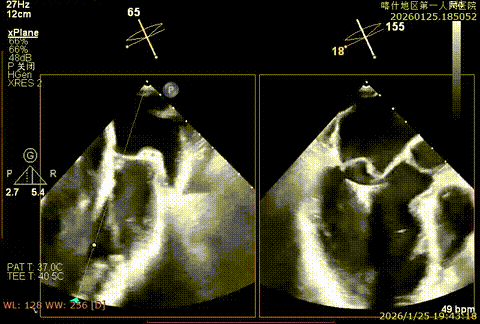

该例患者为DMR类Barlows患者,二尖瓣重度反流,患者1,2,3区均可见脱垂,脱垂主要源于3区,反流主要源于3区。术前制定手术策略:使用一把XTR解决患者瓣叶脱垂与二尖瓣反流。术中进行房间隔穿刺后将XTR-CDS送入左心房,通过操控“M”旋钮,成功将二尖瓣夹定位于2区正上方。在2区进行弹道测试成功后,进行Orientation调整。在3区将二尖瓣夹送入左心室,成功捕捞和夹持瓣叶后缓慢关紧夹臂,解决大部分反流,Saide by Saide L植入第二把XTR。TEE检查见二尖瓣反流程度充分降低至1+,二尖瓣双孔组织桥稳定,跨瓣压差3mmHg,肺静脉逆流改善明显,手术安全结束。

X-plan切面3区后叶脱垂

X-plan切面重度反流

3D enface 观察脱垂

3D enface观察反流